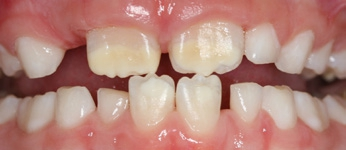

- Im Frontzahnbereich stehen die ästhetischen Einschränkungen, gerade bei schweren Fällen, im Vordergrund.

Behandlung von MIH-Inzisivi

Nur sehr wenige Studien haben die Behandlung von MIH-Inzisivi untersucht. Hierbei stehen oft weniger die Wiederherstellung verloren gegangener Zahnhartsubstanz oder etwaige Hypersensibilitäten im Vordergrund, sondern ästhetische Aspekte. Eine Reihe von Konzepten, die auch zur Korrektur vestibulärer White- Spot-Läsionen oder zur Behandlung von ästhetisch einschränkenden Fluorosen eingesetzt werden, steht zur Verfügung. Remineralisierungstherapien (wie beschrieben mittels CPP-ACP oder reinen fluoridhaltigen Präparaten) sind bisher nur in einer Studie für MIH-Inzisivi eingesetzt worden, um Hypersensibilierungen zu behandeln. Eine solche Remineralisierungsbehandlung ist nahezu „nebenwirkungsfrei“ sowie einfach und günstig (teilweise auch durch den Patienten selbst) durchzuführen. Um zusätzlich eine Einlagerung von Fluoriden zu gewährleisten und damit kariösen Läsionen vorzubeugen, scheint die Applikation fluoridhaltigen CPP-ACPs sinnvoll (Tooth Mousse Plus etc.) [37]. Die zusätzliche Anwendung von Ozon konnte in einer Studie die Wirksamkeit dieser Desensibilierungsbehandlung verlängern, kann aber hinsichtlich ihrer Kostenwirksamkeit und Breitentauglichkeit nicht als Standard gelten. Remineralisierungsbehandlungen können auch zur Therapie ästhetisch einschränkender Defekte eingesetzt werden, sind aber bisher in ihrer Wirksamkeit nicht gut untersucht worden. Ein Nachteil solcher Remineralisierungsansätze ist, dass eine hypermineralisierte Oberflächenschicht aufgebaut wird, die – so sich keine ästhetische Verbesserung einstellt – mitunter mikroinvasive Folgetherapien einschränkt.